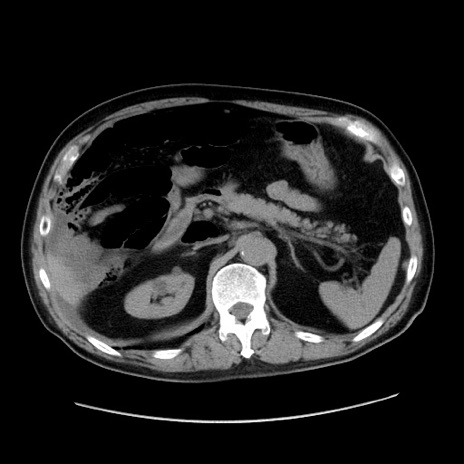

症例30(横断像)

【症例】80歳代男性

【主訴】臍周囲痛

【現病歴】約6時間前から臍下部痛が出現。次第に腹部膨隆・背部痛も生じてきたため来院。背部痛の場所は変化しない。

【身体所見】意識清明、BT 36.3℃、BP  131/87mmHg、P 87bpm、SpO2 100%(RA)、臍周囲自発痛・圧痛あり、反跳痛なし、自発痛部位に一致して板状硬あり、腹部膨隆、腸雑音減弱、CVA tenderness両側陰性。

【データ】WBC 19600、CRP 0.33